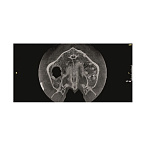

Цифровой панорамный томограф Gendex Pan eXam Plus 2D — это современное и надежное решение для оснащения стоматологической клиники или кабинета. Аппарат предназначен для получения высококачественных двухмерных панорамных снимков зубных рядов, что является основой для планирования лечения, имплантации, ортодонтической коррекции и оценки общего состояния зубочелюстной системы.

- Широкий набор программ сканирования: Аппарат поддерживает различные режимы съемки, адаптированные под конкретные клинические задачи: стандартная панорама, панорама детей, съемка височно-нижнечелюстных суставов (ВНЧС), синус-сканирование и другие.

- Мощное программное обеспечение: В комплекте поставляется интуитивное ПО для управления съемкой, обработки и анализа изображений. Возможности включают в себя масштабирование, регулировку контрастности и яркости, проведение измерений, что облегчает постановку диагноза и консультацию с пациентом.